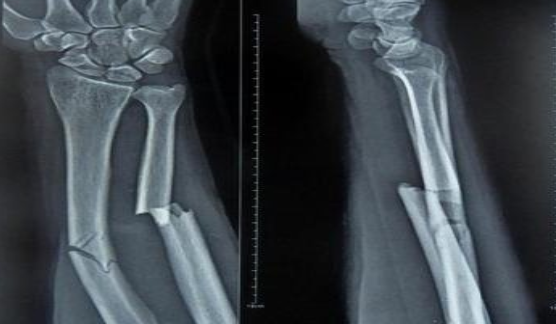

山丹接骨法是一種民間治療手段。山丹縣東樂鄉村民姜多明師從其父,掌握了接骨這門民間絕技。姜多明家族接骨已有上百年歷史,其父親是東樂一帶有名的中醫。改革開放前,由于農村醫療條件有限,這一技術在農村發揮了很大作用,給人民群眾減輕了不少身體上的痛苦。這項接骨技術同時也適用于給牲畜接骨。骨折愈合過程是一個高度復雜和有序的精細過程,姜多明所用的中醫傳統接骨法對骨折愈合起到了其他藥品不可替代的作用,效果很好。這種傳統的接骨方法極為簡潔,不用石膏,只用中草藥加雞蛋清,中藥主要起治療作用,蛋清起固定作用。治療周期較短,小孩子7—8天,傷勢較重的最多1月;成人根據傷勢而定,最多40—50天;牲畜所用天數根據情況而定。 2010年7月6日,山丹接骨法(民間傳統接骨法)被張掖市人民政府列入第二批張掖市非物質文化遺產代表性項目名錄。保護單位:張掖市山丹縣文化館。